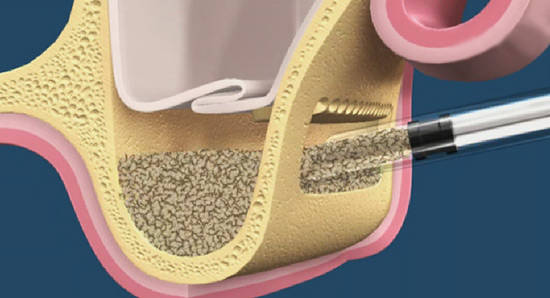

и приступить к подготовке лунки под имплантат:

По существующим правилам, при установке импланта в области фронтальной группы зубов, его ось должна выходить на небную поверхность коронки или режущий край. Чего мы и добиваемся, контролируя процесс с помощью пинов.

Я планирую установить имплантат Dentsply Friadent XiVE диаметром 3.8 и длиной 13 мм. Это оптимальный размер импланта для протезирования боковых резцов.

Установка импланта:

Убираем имплантодержатель. Обратите внимание, что полированная фаска вокруг шейки импланта находится над уровнем костной ткани. Чрезмерное погружение импланта — весьма распространенная имплантологическая ошибка.